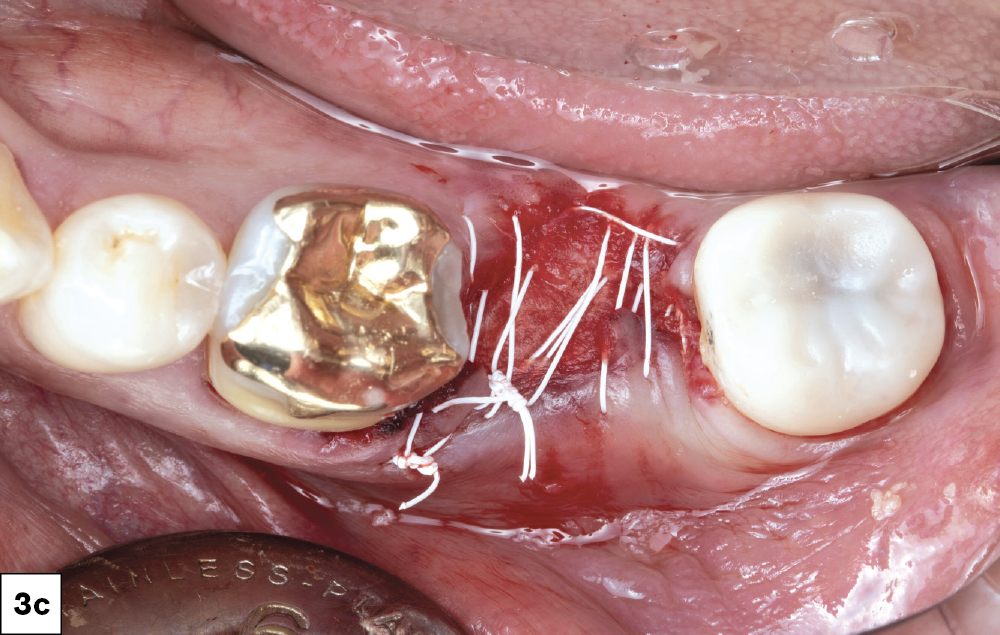

In-office milling is a quickly evolving option for the modern dental practice. With the introduction of a same-day screw-retained option, BruxZir® NOW SRC milling blocks, there’s even more opportunity for optimizing single-unit restoration workflows. In this case study, I’ll demonstrate how this product can be used as part of an efficient workflow for tooth replacement in the posterior. When combined with guided surgery and in-office crown design, this procedure offers reliable results while saving money and significantly cutting down on chair time for dentists.